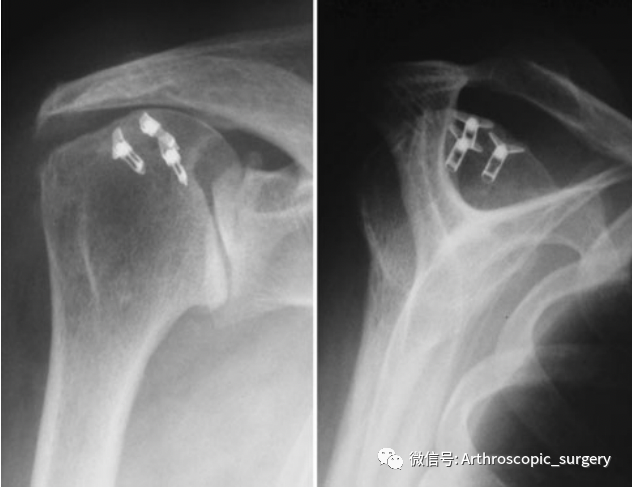

后面陆陆续续有不少的文章进行了相应的报道(下图),统计发现骨坏死多出现在术后4.8月、60岁以上、女性、优势手,在肩关节镜下肩袖修补的同时进行了额外的手术(如:二头肌长头腱的切段/固定、肩峰成形术、肩峰下减压等),但是究其原因暂时没有达成共识,但是大家更多的推测是因为手术中过多的操作导致相应血管的损伤,从而出现缺血性骨坏死。

肱骨近端前方及侧方图示,肩袖修补术中双排缝合锚通常放置的位置(黑色椭圆形);白星标记的是ACHA前外侧分支(AA/AL/5)的入口位置;灰色阴影椭圆形,穿肱骨旋肱后动脉分支的入口位置。HH:肱骨头;GT:肱骨大结节;LT:肱骨小结节;IG:结节间沟

因此,在肩关节镜下操作时,一定要切记在这些容易损伤到血管的区域一定要仔细操作(尤其是进行二头肌长头腱的操作时,对于AL/AA/5分支的保护),避免不必要的损伤导致的骨坏死发生。同时有研究表明,过多的植入锚钉可能会导致肱骨大结节内乏血管区血供的进一步减少,从而导致骨坏死的发生。但是也有很多研究证明,有一些部分患者并没有锚钉的植入,也出现了骨坏死;同时也有研究证实并不会因为锚钉的过多植入,会增加肱骨头坏死的可能。